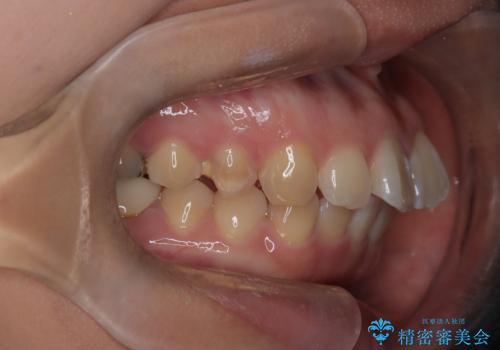

- 口元が出ている(突出している)ことを気にされて来院されました。精密な検査の結果、前歯を大きく後退させるスペースが必要と診断。患者様の**「前歯を下げたい」という強いご要望に応えるため、上下左右の第一小臼歯を抜歯し、そのスペースを利用して前歯を奥へ移動させる治療計画を立案しました。また、人目を気にせず治療できるよう、上顎に裏側矯正、下顎に表側矯正を組み合わせたハーフリンガル矯正**を提案しました。

今回の矯正治療では、前歯を大きく後退させるスペースを確保するため、計画通り上下左右の第一小臼歯を抜歯しました。装置には、上顎には目立たない裏側矯正(舌側矯正)を、下顎には透明な審美ブラケットを使用するハーフリンガル矯正を採用しました。抜歯によってできたスペースを最大限に活用し、前歯を効率よく後方へ移動。治療の結果、口元の突出感が大幅に解消され、Eライン(横顔の美しさの基準)も改善しました。人目を気にすることなく治療を完遂し、自信の持てる美しい横顔を獲得していただけました。